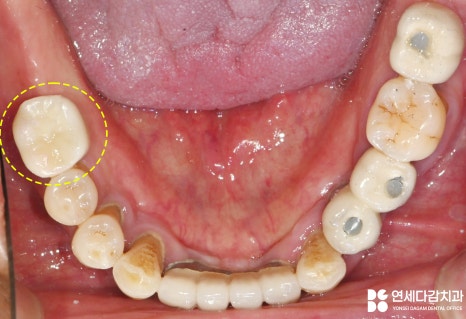

그러나 맞지 않는 틀니를

사용하다 보니,

가락시장역 치과 에서 표시한

부위처럼

잇몸에 상처가 나기도 하죠.

위와 같은 치료를 통해

얻을 수 있는 개선점은

저작력이 강해져

전에는 제대로 먹을 수 없었던

고기를 먹을 수 있습니다.

또한

입천장 전체를 덮는 전체 틀니는

발음이 방해되었는데,

고정성 보철은 이런 문제를

해결할 수 있었습니다.

팔자 주름이 깊게

생겼던 것도 개선되어

안모에도 변화를 줄 수 있었죠.